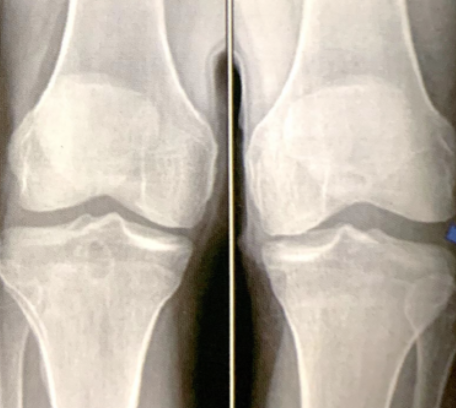

膝關(guān)節(jié)外側(cè)結(jié)構(gòu)由數(shù)條韌帶和肌腱組成,其中以外側(cè)副韌帶及后外側(cè)結(jié)構(gòu)尤為重要,主要起到限制膝關(guān)節(jié)內(nèi)翻、外旋及前后位移的作用。單純性外側(cè)副韌帶III°撕裂或復(fù)合性損傷需盡快進(jìn)行手術(shù)修復(fù),使用PEEK帶線錨釘將外側(cè)副韌帶縫合修復(fù)至附著處,外側(cè)副韌帶體部損傷、無法解剖修復(fù)的情況下及慢性損傷需進(jìn)行韌帶重建術(shù)。

1.單純外側(cè)副韌帶III°撕裂;

2.側(cè)副韌帶損傷合并其他韌帶、血管、神經(jīng)復(fù)合性損傷。